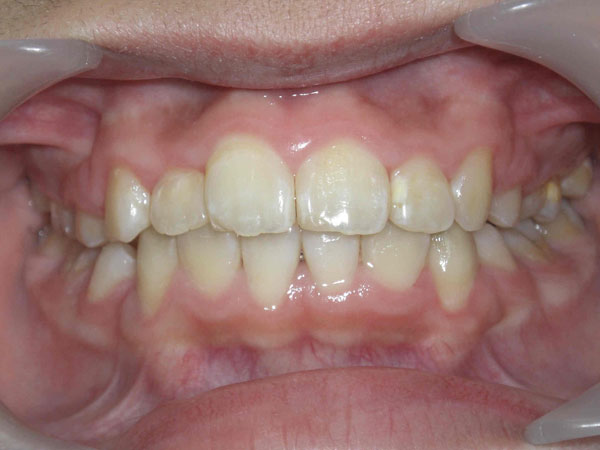

上の前歯が下の前歯より極端に前に出ている噛み合わせの状態を上顎前突(出っ歯)と言います。

上顎前突の噛み合わせでは上あごの前歯が下あごの前歯と噛み合いません。

幼児期の指しゃぶりが原因になることもあります。